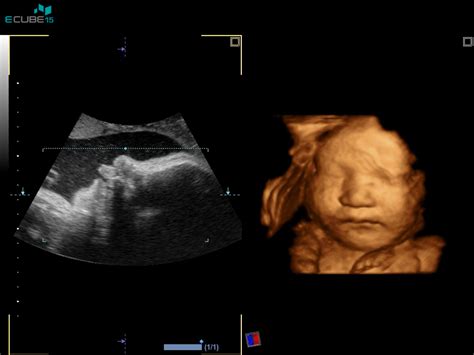

Oddelek za perinatologijo UKC Maribor se zaveda pomena zgodnjega odkrivanja in obvladovanja morebitnih zapletov v nosečnosti. Zato so uvedli vrsto sodobnih diagnostičnih metod. Med najpomembnejše sodijo ultrazvočni pregledi, ki omogočajo natančno določitev pričakovanega termina poroda že med 11. in 14. tednom nosečnosti. Novejše raziskave so pokazale, da merjenje pretokov krvi skozi žile, ki prehranjujejo maternico, lahko napove povečano tveganje za preeklampsijo. Pravočasna uvedba aspirina pred 16. tednom nosečnosti je dokazano zmanjšala pogostost preeklampsije za polovico, medtem ko kasnejša uvedba nima enakega učinka.

Posebno pozornost namenjajo genetskim nepravilnostim ploda. Poleg že uveljavljene amniocenteze, ki je invazivni postopek odvzema plodovnice, so uvedli tudi biopsijo horionskih resic, ki omogoča izjemno podrobno analizo genetskega stanja ploda. Z uvedbo neinvazivne prenatalne diagnostike s prostocelično DNA ploda v materini krvi, ki še bolj zanesljivo kot merjenje nuhalne svetline odkrije kromosomske nepravilnosti, zlasti trisomije, z znatno nižjim številom lažno pozitivnih rezultatov, so zmanjšali potrebo po nepotrebnih invazivnih posegih.